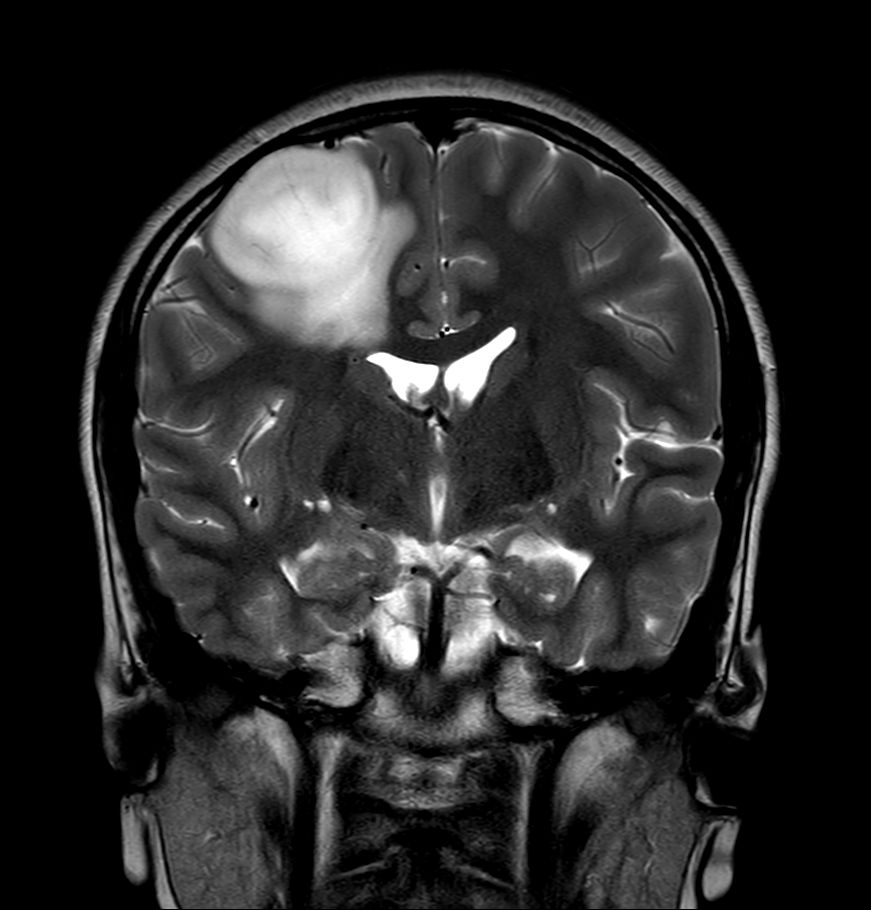

T2w TSE MultiVane XD

-

3D T2w FLAIR - Coronal Reformat Compressed SENSE